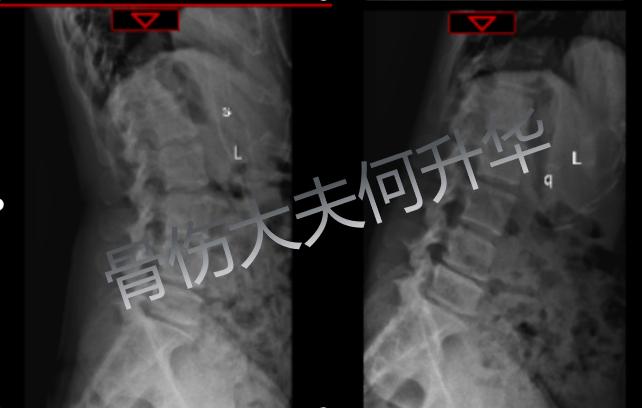

入院检查X线动力位提示

腰4/5腰5/骶1椎间不稳